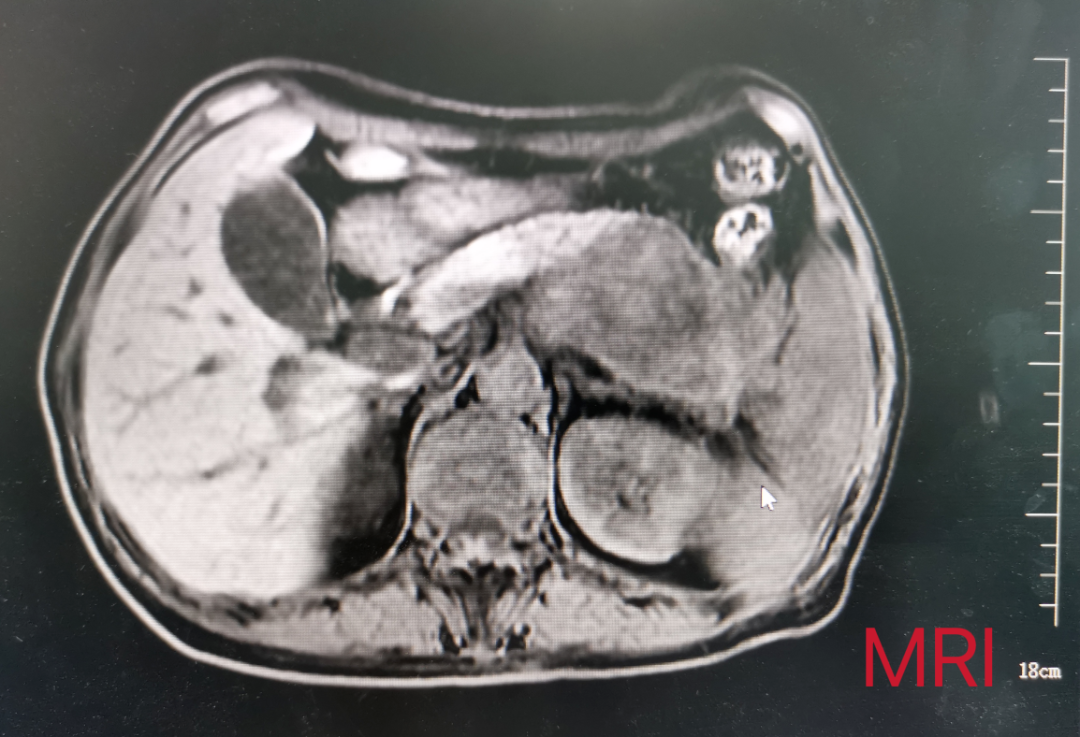

患者女性,57岁,因“间断左上腹疼痛3月余”入院,既往无特殊疾病史。入院后完善相关检查提示:胰腺尾部占位性病变,约8cm×5cm,考虑囊腺癌,累及脾动静脉和腹腔干可能性大。肠镜发现结肠距肛门30cm可见一肿物。患者腹痛逐渐加重,通过术前充分评估和讨论,祁向军主任认为结肠肿物为胰腺肿瘤侵犯所致,在与患者及患者家属充分沟通后,决定立即为患者施行手术治疗。考虑血管侵犯可能以及肿瘤较大,决定为其行胰体尾+脾根治性扩大切除术,包括胰体尾、脾、部分受侵结肠的切除以及周围腹腔淋巴结的清扫,并且备术中腹腔干的切断以及置换。手术成功完成,患者胰体尾、脾、和部分结肠完整切除,现患者已康复出院。